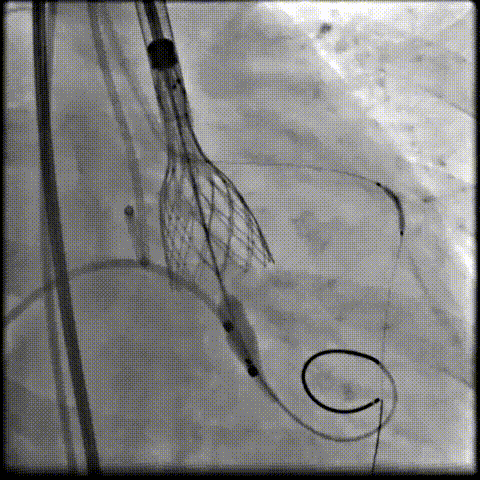

术中影像

根部造影可见返流;20mm球囊预扩,LCA灌注缝隙狭小

预置LCA保护;第一次释放,

团状钙化挤压导致瓣膜(AV23)少量下滑

回收后重新定位,第二次释放,

瓣膜(AV23)深度仍未达到最佳预期

完全回收,第三次定位释放,瓣膜(AV23)位置良好

瓣膜工作位释放“烟囱支架”;

瓣膜(AV23)完全释放后,“烟囱支架”后扩

最终造影,“烟囱支架”显影清晰,瓣膜形态及LCA灌注良好